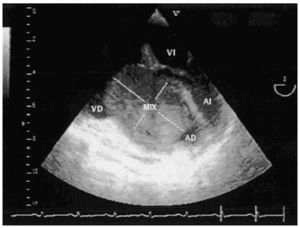

Mujer de 49 años con antecedentes personales de HTA y enfermedad pélvica inflamatoria sin secuelas. Ingresa por dolor abdominal, nicturia y edemas en miembros inferiores de 2 meses de evolución. En la ecografía realizada se apreció una masa abdominal de gran tamaño compatible con mioma uterino. Se intervino de forma programada con histerectomía total ampliada. Dos días después desarrolló hipotensión arterial, oliguria y marcado aumento de los edemas, por lo que finalmente fue preciso su ingreso en UCI. Destacaban signos de bajo voltaje en el ECG, mínima cardiomegalia y ligero derrame pleural derecho en la radiografía de tórax (figs. 1 y 2). Se realizó ecocardiografía transesofágica de urgencia donde se objetivó una masa en la aurícula derecha de 3,7 ×7 cm, de consistencia heterogénea, con punto de implantación en zona inferior del septo interauricular, que invadía el ventrículo derecho y ocupaba la mayor parte del anillo valvular auriculoventricular (fig. 3). La interpretación ecocardiográfica fue de trombo intracardíaco o mixoma auricular derecho. La paciente se intervino quirúrgicamente y se confirmó este último diagnóstico.

Figura 2.